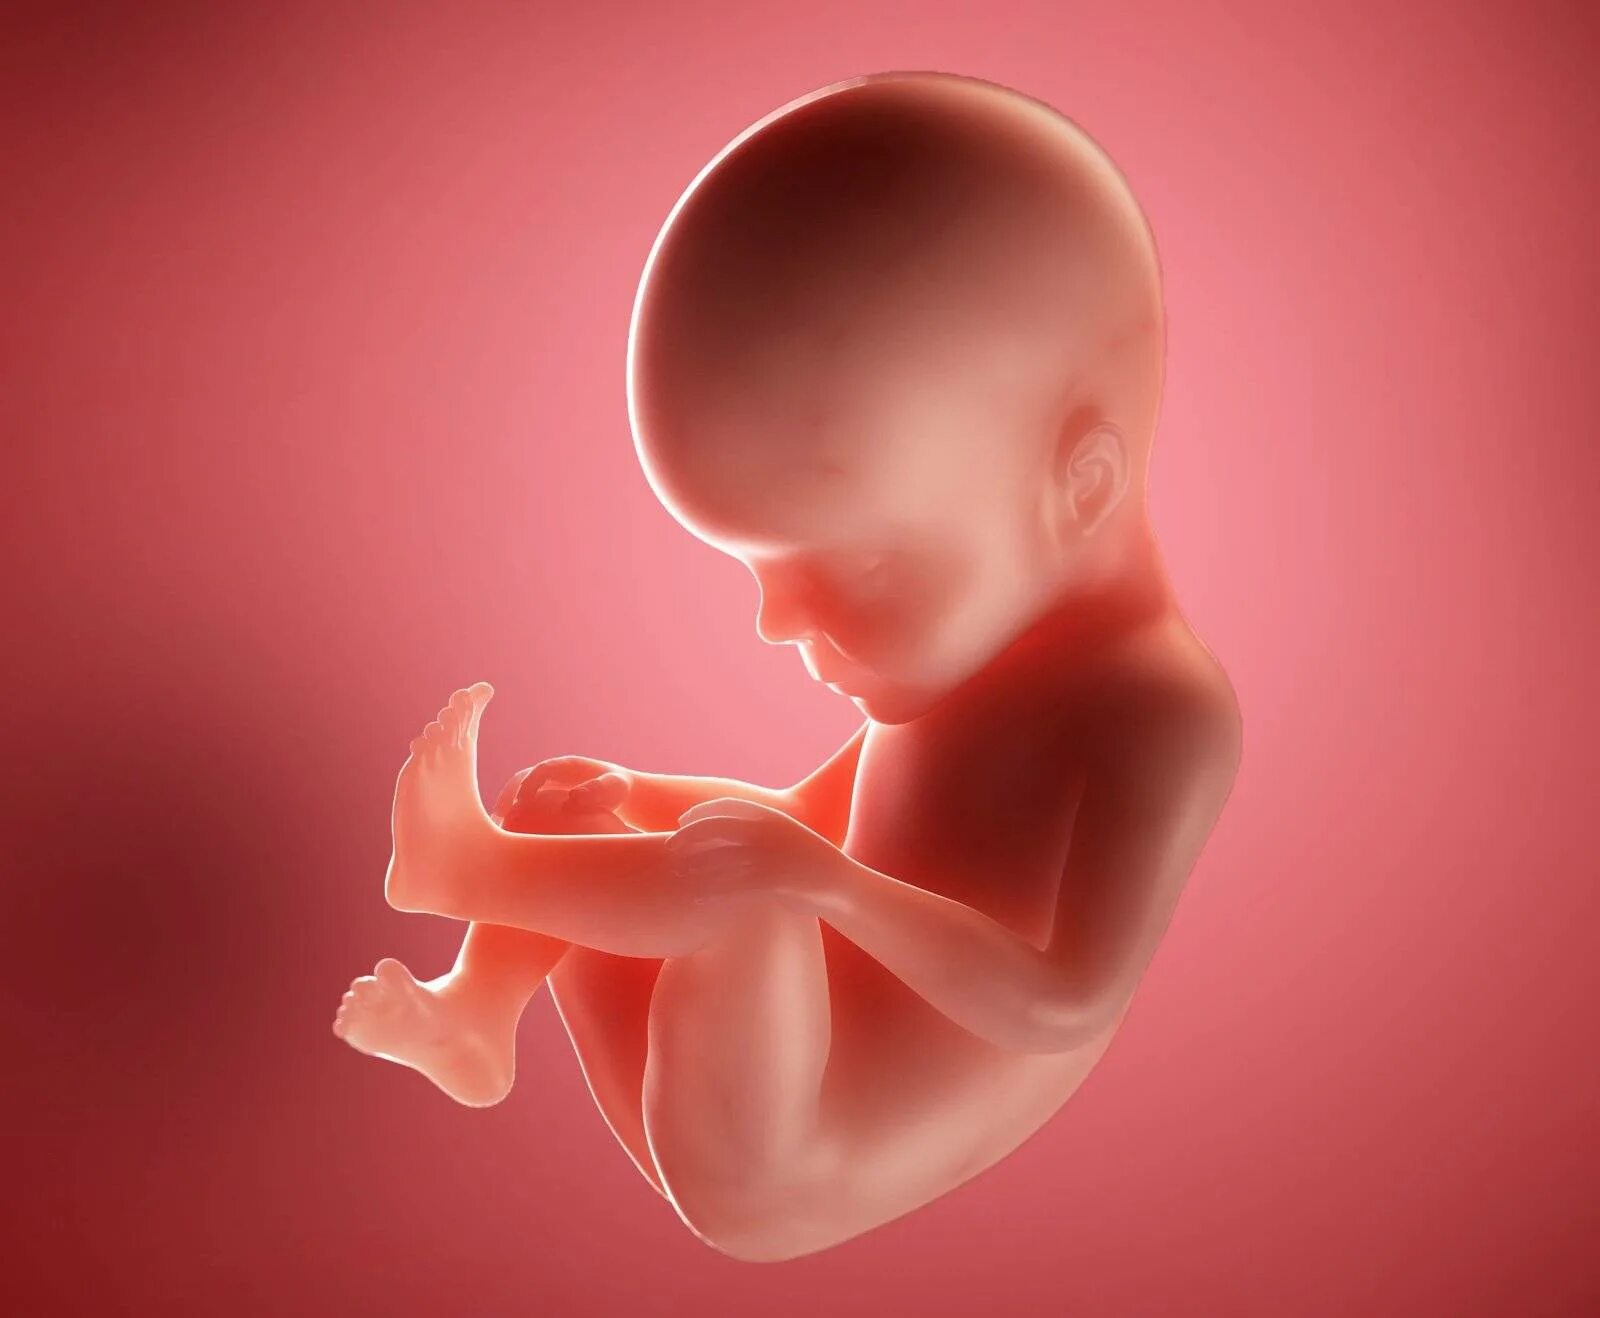

Ощущения 27 неделя